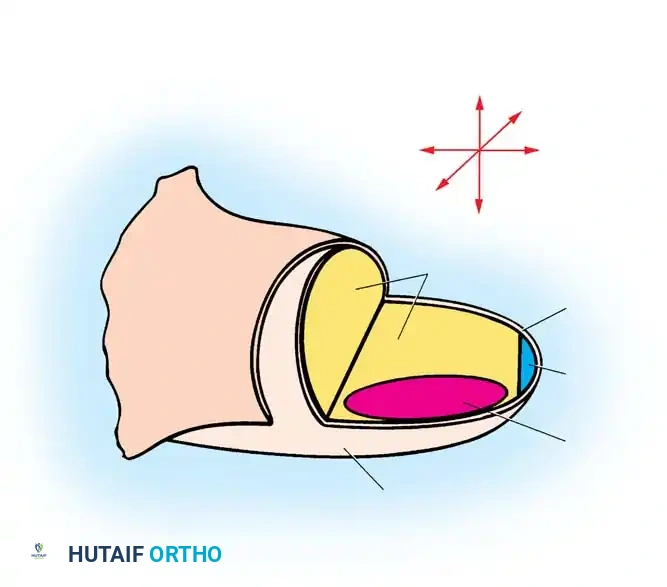

- The Apical Ectodermal Ridge (AER): Located at the distal tip of the limb bud, the AER is responsible for proximal-to-distal growth. It secretes Fibroblast Growth Factors (FGFs) that maintain the underlying mesoderm in a highly proliferative state known as the progress zone.

Fig. 76-1 Limb bud. The apical ectodermal ridge extends from anterior to posterior along the dorsal/ventral boundary of the growing limb bud. Proximal to the AER is the progress zone. Within the posterior mesoderm is the zone of polarizing activity. These centers are highly interconnected; limb patterning and growth depend entirely on their coordinated function.